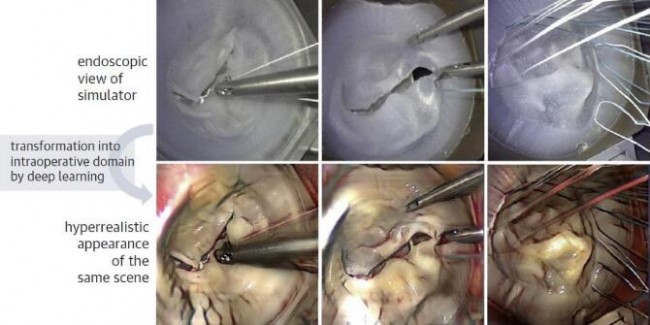

AI与3D打印技术相结合,可以打印出个体化解剖模型,进而促进精准医疗。Engelhardt等通过使用深度神经网络从腔镜视野中学习术中关键操作和步骤,展示了AI强大的微创手术培训能力。计算机网络可从腔镜二尖瓣修复手术中获取其关键特征(包括纹理不均的组织结构、血流情况、器械以及缝线使用等),从手术模拟中获取其显著特征(如瓣膜复制品的硅胶表面、器械以及缝线使用等)。AI训练的目的就是通过学习实际手术和模拟手术两者之间的映射联系,使得模拟手术的操作视野更接近于实际操作视野。该方法被称为“超现实主义”,是增强现实的一种形式,即通过产生原始图像中本不存在细节的模拟现实,来实现比真实手术更为真实的渲染效果,进而达到提升手术训练质量的目的[58]。图12展示了使用二尖瓣人工硅胶瓣膜进行介入手术训练的超现实主义。

基于超现实主义和AI模拟在医疗器械培训中展现出的潜在适应性,使得未来它们可能成为新技术蓬勃发展的基础。通过在手术模拟中集成完整的心脏瓣膜模型,AI技术能明显提升术者对手术器械操作和术中技术应用的信心[21,22]。在深度学习框架中,将AI应用于术中TEE处理,允许计算机对自动客观获得的TEE图像进行质量评估和反馈。例如,在TAVR培训的过程中,计算机通过对于术者手术操作和器械操作的自动化评估已经发现了某些客观指标(如新手和专家在操作时间、速度、加速度等方面的差异)是可被计算机复制的[22]。未来,实时3D-TEE数据与机器学习和AI的结合,将有助于提供更客观有效的介入影像医师和术者培训模式。